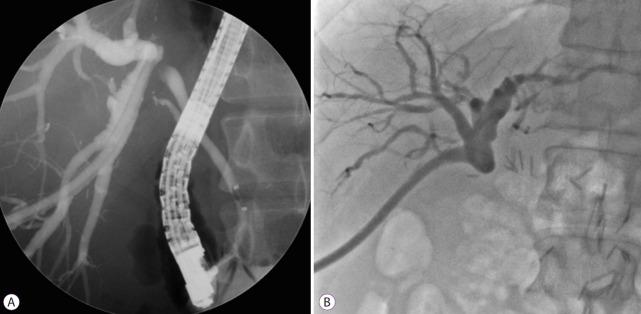

磁压缩吻合术治疗移植后胆管狭窄

A number of different conditions can lead to a bile duct stricture. These strictures are particularly common after biliary operations, including living-donor liver transplantation. Endoscopic and percutaneous methods have high success rates in treating benign biliary strictures. However, these conventional methods are difficult to manage when a guidewire cannot be passed through areas of severe stenosis or complete obstruction. Magnetic compression anastomosis has emerged as an alternative nonsurgical treatment method to avoid the mortality and morbidity risks of reoperation. The feasibility and safety of magnetic compression anastomosis have been reported in several experimental and clinical studies in patients with biliobiliary and bilioenteric strictures. Magnetic compression anastomosis is a minimally traumatic and highly effective procedure, and represents a new paradigm for benign biliary strictures that are difficult to treat with conventional methods.

多种不同情况可导致胆管狭窄。这些狭窄在胆道手术后尤为常见,包括活体供肝肝移植。内镜和经皮方法在治疗良性胆管狭窄方面成功率较高。然而,当导丝无法通过严重狭窄或完全梗阻区域时,这些传统方法难以实施。磁压缩吻合术已成为一种替代性的非手术治疗方法,以避免再次手术的死亡率和发病率风险。多项针对胆管-胆管和胆管-肠吻合口狭窄患者的实验和临床研究已报道了磁压缩吻合术的可行性和安全性。磁压缩吻合术是一种微创且高效的手术,代表了传统方法难以治疗的良性胆管狭窄的一种新范例。